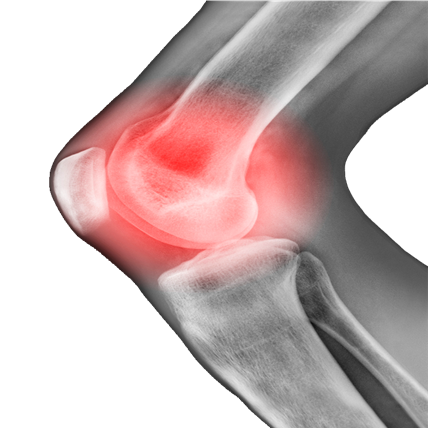

膝关节退化症状

无论你年龄多大,都要知道关节退化时,基本累及膝关节周围所有结构,可表现为关节软骨磨损脱落、关节边缘骨赘生成、滑膜炎症、韧带和关节囊挛缩或松弛,更要知道出现以下症状时,要寻求治疗:

膝盖反复疼痛

上下楼梯或蹲起时,疼痛明显

晨起时膝盖疼痛发僵,活动后缓解

膝关节总出现“咔咔”声音,有摩擦感

膝关节出现肿胀

严重时,出现O型腿或X型腿,或原有关节畸形变重